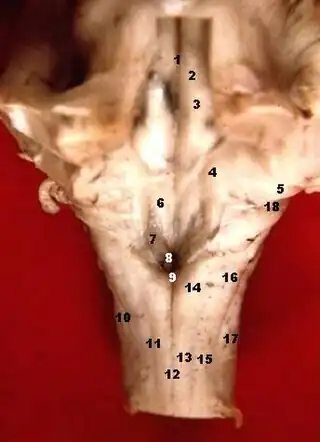

La fosa romboidal, suelo del cuarto ventrículo o fosa romboidea ([TA]: fossa rhomboidea) es la pared anterior y el suelo del cuarto ventrículo cerebral, y es la parte posterior del puente de Varolio y la médula oblongada.

Está cubierta por una fina capa de sustancia gris continua con la médula espinal. Superficial a esta lámina se encuentra una delgada lámina de neuroglía que constituye el epéndimo, compuesta por una monocapa de epitelio ciliado cuyas células se conocen como ependimocitos.

La fosa consta de tres partes:[1]

- La parte superior es de forma triangular y está limitada lateralmente por el pedúnculo cerebeloso superior; su ápice, dirigido hacia arriba es continuo con el acueducto cerebral, su base está representada por una línea imaginaria a nivel del límite superior de la fóvea superior.

- La parte intermedia se extiende desde este nivel a las porciones horizontales de las tenías del ventrículo. Es estrecha en la zona superior, donde está limitada lateralmente por el pedúnculo medio, pero se ensancha hacia abajo y se prolonga en los recesos laterales del ventrículo.

- La parte inferior es triangular y su ápice dirigido hacia abajo, llamado el calamus scriptorius, es continuo con el canal central de la parte cerrada de la medula oblongada.

El sulcus limitans o cisura limitante forma el límite lateral de la eminencia medial.